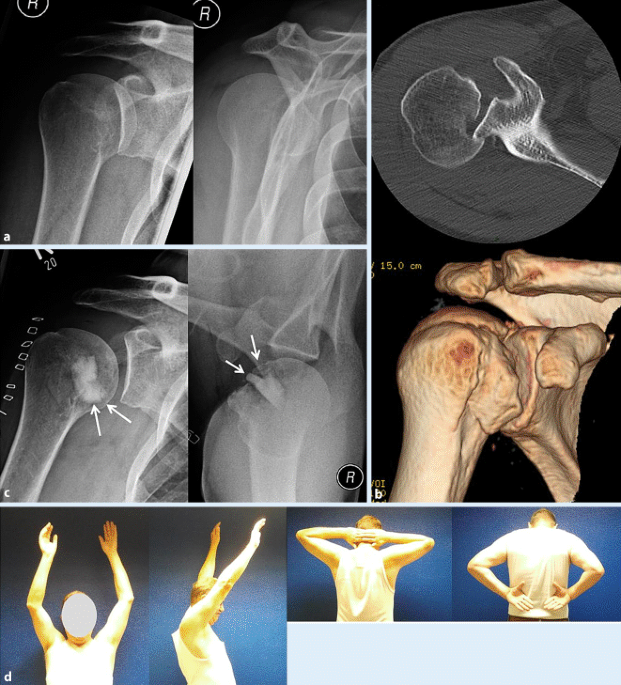

Proximaler Oberarm | SpringerLink